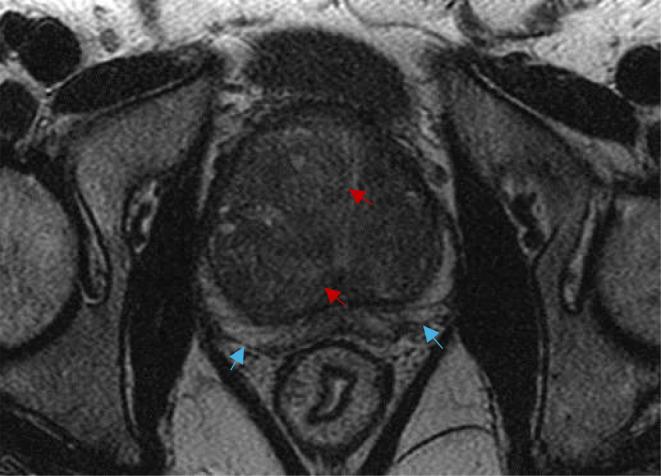

Radiology of fibrosis part III: genitourinary system.

Fibrosis is a pathological process involving the abnormal deposition of connective tissue, resulting from improper tissue repair in response to sustained injury caused by hypoxia, infection, or physical damage. It can impact any organ, leading to their dysfunction and eventual failure. Additionally, tissue fibrosis plays an important role in carcinogenesis and the progression of cancer.Early and accurate diagnosis of organ fibrosis, coupled with regular surveillance, is essential for timely disease-modifying interventions, ultimately reducing mortality and enhancing quality of life. While extensive research has already been carried out on the topics of aberrant wound healing and fibrogenesis, we lack a thorough understanding of how their relationship reveals itself through modern imaging techniques.This paper focuses on fibrosis of the genito-urinary system, detailing relevant imaging technologies used for its detection and exploring future directions.

纤维化是一种病理过程,涉及结缔组织的异常沉积,是由于缺氧、感染或物理损伤引起的持续损伤导致的组织修复不当引起的。它可以影响任何器官,导致其功能障碍和最终衰竭。此外,组织纤维化在致癌作用和癌症进展中起着重要作用。早期准确诊断器官纤维化,并定期进行监测,对于及时进行疾病修饰干预至关重要,最终可以降低死亡率并提高生活质量。虽然已经对异常伤口愈合和纤维化发生进行了广泛的研究,但我们对它们之间的关系如何通过现代成像技术表现出来仍缺乏全面的了解。本文重点介绍了生殖泌尿系统的纤维化,详细介绍了用于检测的相关成像技术,并探讨了未来的方向。